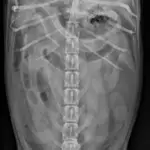

Radiographic Findings: The stomach is gas-filled. Small intestines are diffusely and moderately distended with fluid and gas (white arrows). The colon is also filled with gas and some mottled-to-homogeneous soft tissue opacity (black arrow). Remaining organs and serosal detail appear normal.

Abdominal radiographs: Left lateral (above) and ventrodorsal views (left)